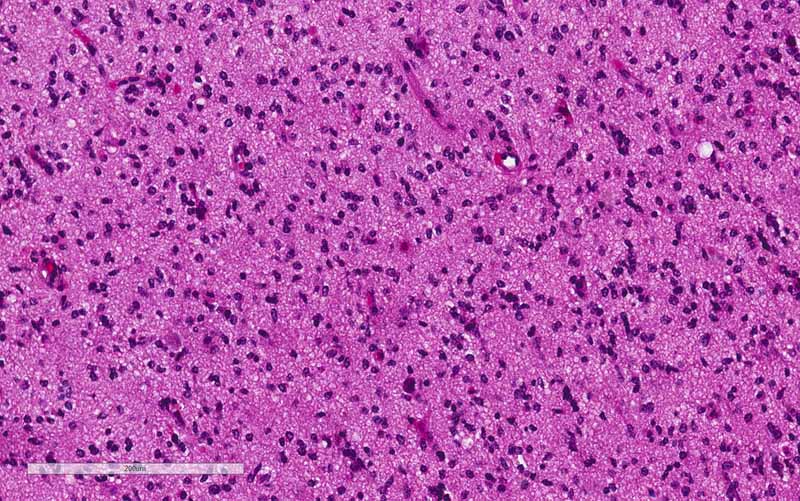

Pathology of the Case: The tumor seems to have a biphasic pattern. In some of the areas, it has the classic features of a neoplastic glial neoplasm (Panel C, D,, & E). These areas show a rather homogenous proliferation of neoplastic glial cells with high-grade nuclei. Note the spongiotic background (Panel E) and this probably are the edematous area demonstrated on FLAIR. In the remaining parts of the specimen, however, there are islands of large, bizarre cells that are well-demarcated (Panel F) from the surrounding tumor with features in Panel C and D. These large cells are characterized by a large variation in size with many of them a centrally located inclusion (Arrow in Panel G) that seems to have pushed the nucelus to an eccentric location. While some of them are binucleated (Arrow in Panel G), multinucleated tumor cells are not common. The nuclei are enlarged, pleomorphic, and with large and eosinophilic nucleoli. These cells are rhabdoid cells. Endothelial proliferation is also present (Arrow in Panel F). There is some necrosis (not shown). On immunohistochemistry, the tumor cells are negative for IDH1-R132H consistent with no mutation. The tumor cells are strongly positive for ATRX consistent with wild-type ATRX. Only occasional tumor cells are positive for p53 indicating no mutation in p53. The Ki67 labeling is much higher, up to about 30%, in the rhabdoid area in comparison to the areas with features of classic high-grade glioma (Panel H & I).

Comment on pathology: The rhabdoid area is well-demarcated fromt he surrounding high-grade glioma with a pushing margin. This phenomenon is most consistent with a high-grade/rhabdoid transfromation arising from the surrounding high-grade glioma areas. This kind of well-demarcated high-grade changes is more commonly seen in malignant/high-grade transformation in sarcomas.

Next generation sequencing panel study and chromosome microarray study were performed in this case with a block containing the rhabdoid changes. There was no loss of SMARCB1(INI1) or SMAECA4(BRG1) were demonstrated by next generation sequencing. Chromosomal changes included gain of chromosome 7, EGFR amplification, CDKN2A/B homozygous deletion, and heterozygous loss of chromosome 10. There was also mutation of TERT promoter. These features were classic for a glioblastoma. The rhabdoid changes stood out distinctly in a background of high-grade glioma.  The significant increase in Ki67 labeling in the rhabdoid area. Both features supported that the rhabdoid component was a high-grade transformation arising from the existing glioma. With all of these features taken into consideration, this is a case of glioblastoma with rhabdoid changes.